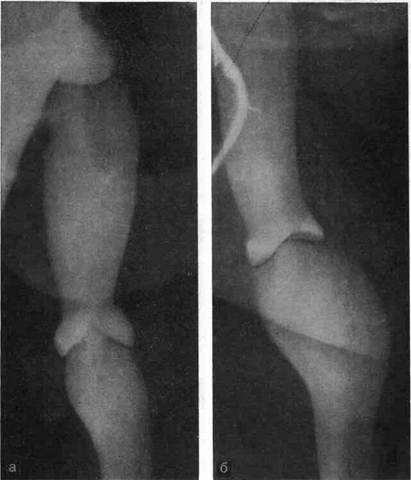

Рис. 24. Флебограммы нормально функционирующих клапанов глубоких вен бедра (а) и голени (б)—ретроградное контрастировать.

В клинической практике наблюдаются различные варианты, когда встречается относительная недостаточность тех или иных клапанов, что четко определяется при ретроградной флебогра-фии. Во время пробы Вальсальвы при флебоскопии видно, как контрастированная кровь устремляется ретроградно через недостаточные клапаны большой подкожной и бедренной вен или только по одной из названных вен. В случаях недостаточности клапанов глубоких и поверхностных вен контрастное вещество, введенное посредством пункции в бедренную вену при пробе Вальсальвы, распространяется по глубоким и поверхностным венам до средней трети голени. При полноценных клапанах ретроградного распространения контрастного вещества не происходит. При этом четко контрастируется клапан, ограничивающий ретроградный кровоток (рис. 24, а, б).